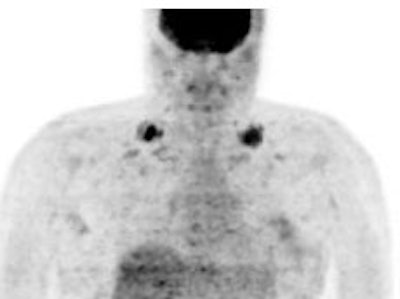

Brown Fat: Prominent, symmetric supraclavicular tracer uptake was seen in this patient without a corresponding CT finding. Uptake in this area has been felt to be related to the presence of "brown" fat. |